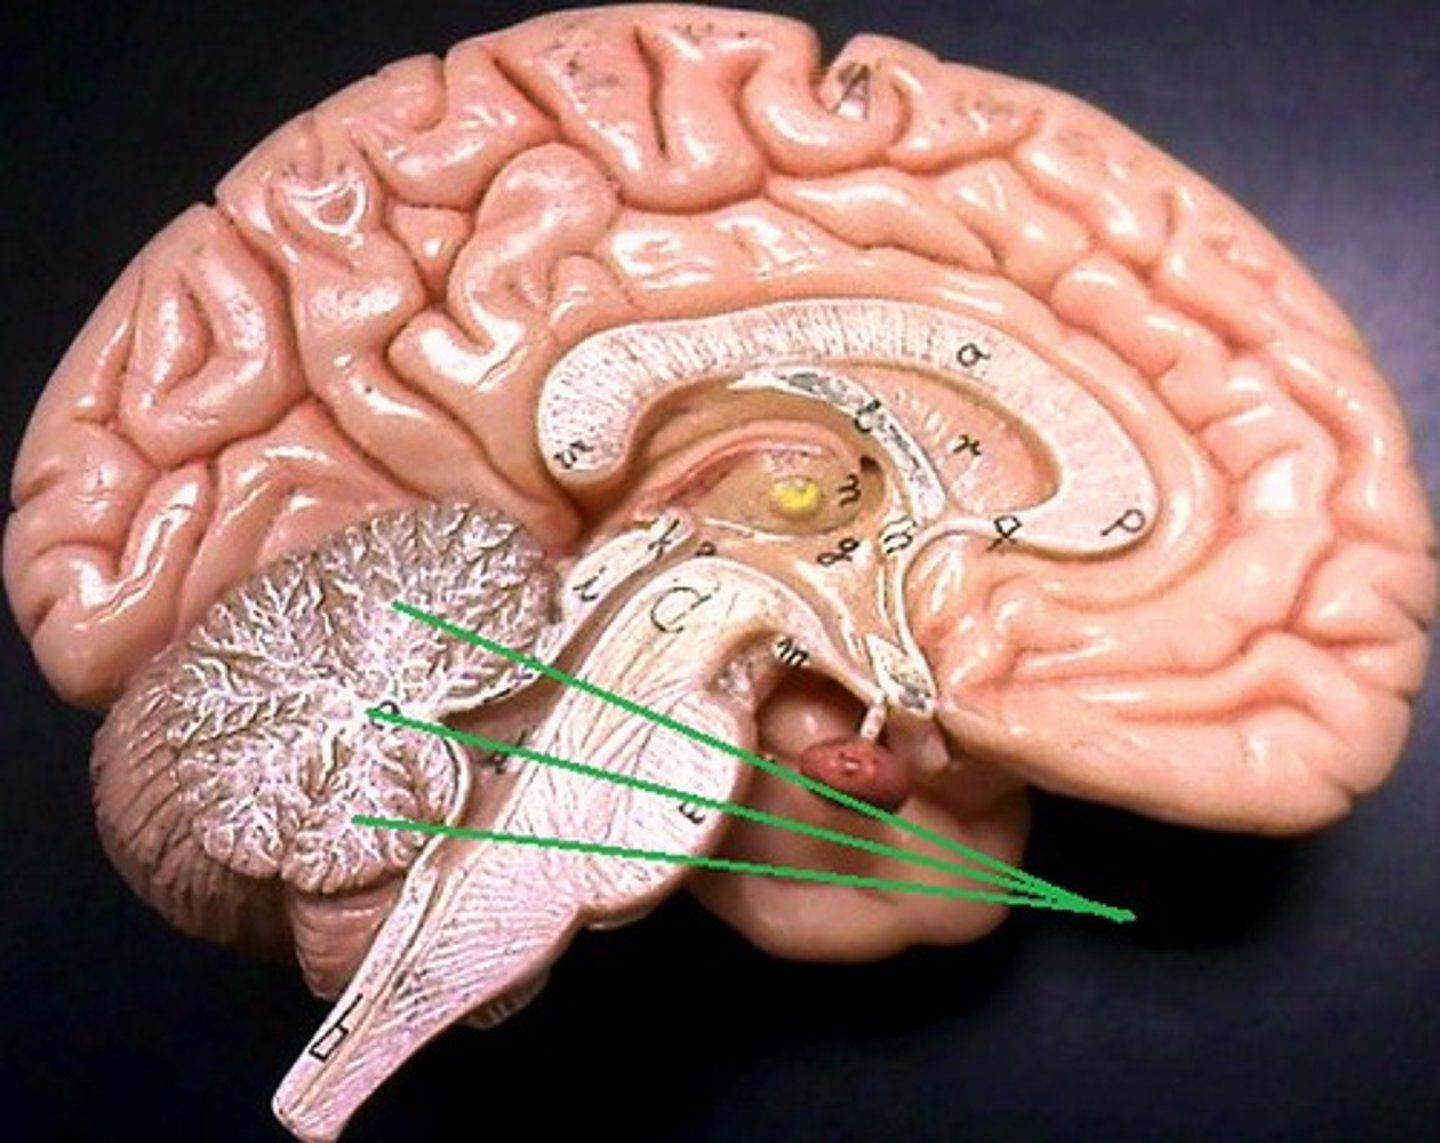

Thalamus

Hypothalamus

Mammillary body

Pituitary gland

Pineal gland

Cerebellum

vermis

cerebellar peduncles

cerebral aqueduct

third ventricle

fourth ventricle

pons

midbrain

medulla oblongata

arbor vitae